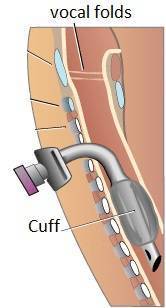

How do you connect a nebulizer to a Trach?

Attach the tubing to the nebulizer machine. Disconnect the ventilator at the connection between the vent filter and the person's trach tubing. Connect the nebulizer T-connector to the vent filter and then connect the other end to the person's trach tube. Turn the nebulizer machine on. The medicine in the cup will begin to turn into a fine mist.

What is the nebulizer connected to?

The nebulizer is connected to the tracheal collar or a T-piece added to the respirator circuit that allows the child to inhale the medication .

What is a small volume nebulizer?

Small volume nebulizer: Allows delivery of an aerosol treatment. A nebulizer is a medical device that contains a medication in liquid form; it is connected to an air compressor that helps to convert the medication into an aerosol that can easily be inhaled into the lungs. Different types of nebulizers exist; your child’s health care team will ...